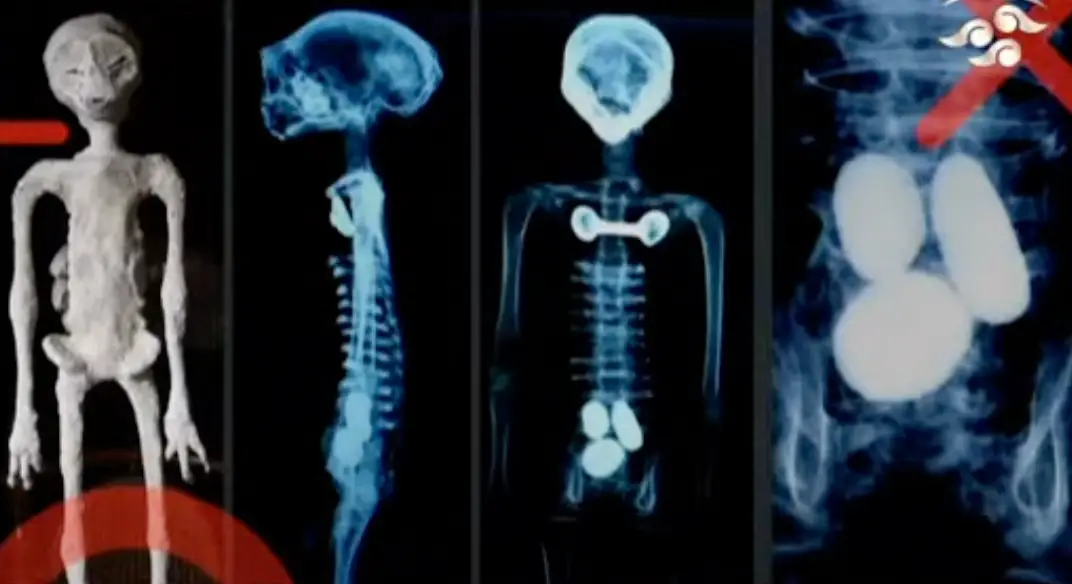

Doctors in Mexico have said the alleged ‘alien corpses’ recently shared with the world have ‘no relation to human beings’.

The two mummified corpses were displayed in windowed boxes, having been retrieved from Cusco in Peru.

Naturally, people didn’t take Maussan at his word and tests have since been conducted on the remains by experts at the Noor Clinic.

The results of the test were shared by Doctor José Zalce Benitez, the director of the Health Sciences Research Institute in the secretary of the Mexican navy’s office, who said that the so-called bodies belonged to single skeletons and had not been assembled.

He said the tests showed that ‘there is no evidence of any assembly or manipulation of the skulls’.

Benitez added: “I can affirm that these bodies have no relation to human beings.”